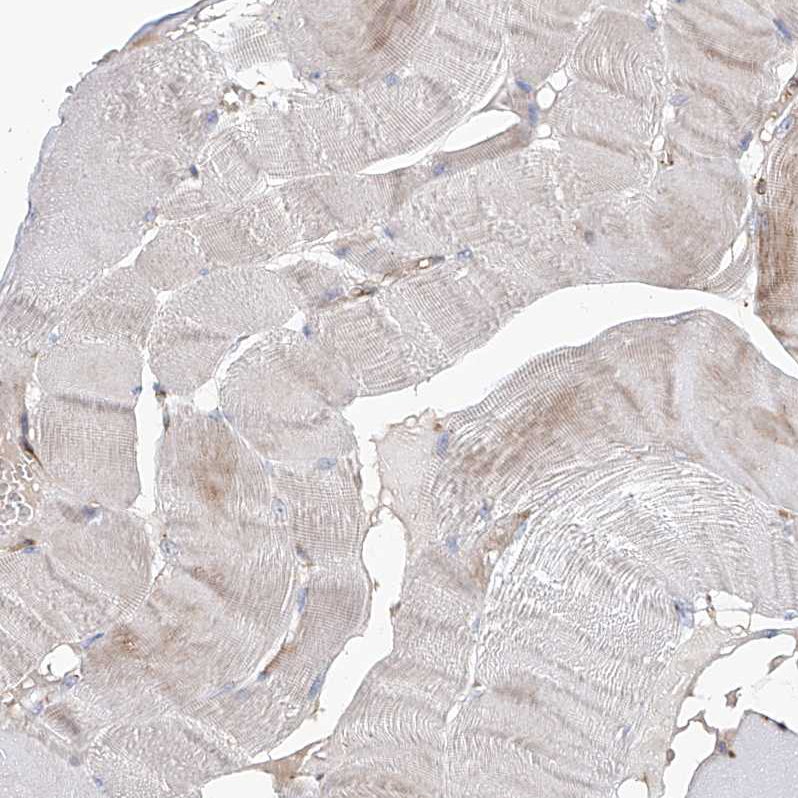

Immunohistochemical staining of human kidney shows strong positivity in cytoplasm granular in cells in tubules.